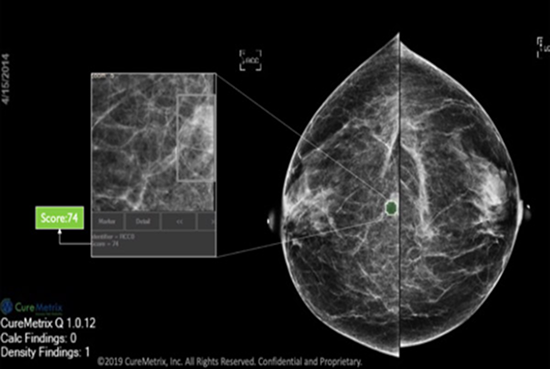

cmAssist has the ability to quickly detect key regions of interest on a mammogram, and accurately quantify and label anomalies as suspicious or, instead, verifiably benign. cmAssist does this by searching all the views of a digital 2D-mammogram for abnormal areas of density, mass or calcification and by highlighting suspicious areas requiring further analysis. Once anomalies are flagged in the system, cmAssist then marks the mammogram and highlights the identified anomalies.

The software also generates a unique, data-driven neuScore™ that provides radiologists with a quantitative measure of suspiciousness in a marked region of interest, ranging from 0 (least suspicious) to 100 (highly suspicious). This score can be tracked over time to evaluate the stability or evolution of identified anomalies.